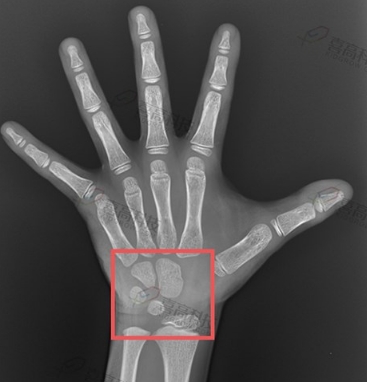

骨齡評估系統(tǒng)

骨齡評估系統(tǒng)是一種用于評估兒童和青少年骨骼發(fā)育程度的醫(yī)療設(shè)備。該系統(tǒng)通過分析手腕部X光片中的骨骼發(fā)育特征,與標(biāo)準(zhǔn)骨齡圖譜進(jìn)行比對,從…